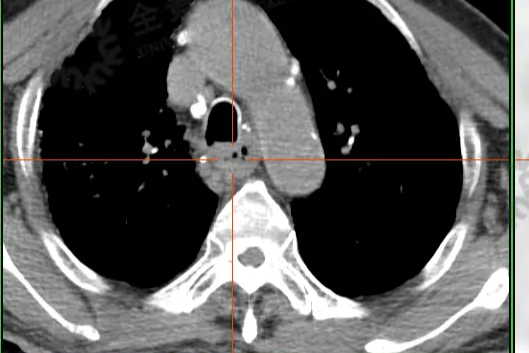

高血压患者的综合健康管理之路